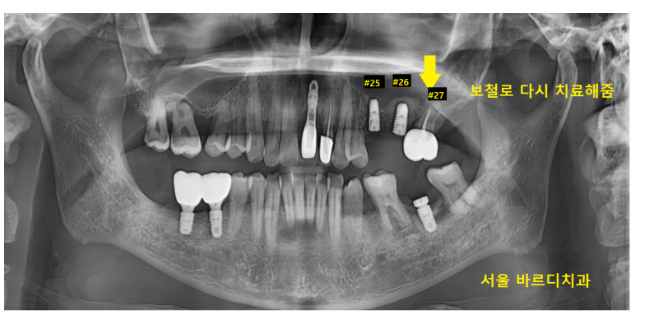

묶어뒀던 치아를 벗겨낸 모습입니다.

문제가 있던 치아는 왼쪽 사진

누가 봐도 까맣게 보이죠??

충치가 심한 치아는 살리기 어려워 발치 후 임플란트

오른쪽에 있는 사진은

벗겨 냈을 때 내부가 멀쩡해 보여

다시 씌워서 사용하기로 설명 드렸습니다.